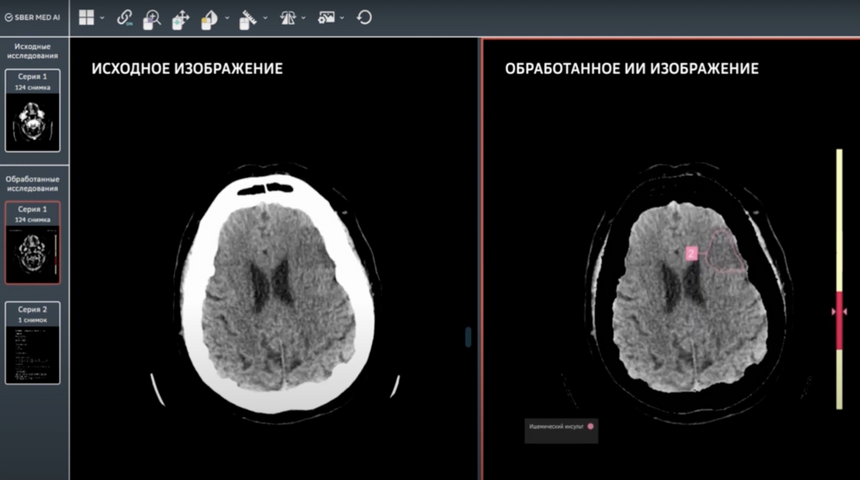

Компания СберМедИИ вместе с Лабораторией искусственного интеллекта Сбера разработала новый AI-сервис под названием «КТ головного мозга». Этот сервис предназначен для поддержки врачей при диагностике инсульта на основе данных компьютерной томографии.

Алгоритм сервиса автоматически анализирует КТ-снимки головного мозга, определяет признаки инсульта и внутричерепных кровоизлияний, выделяет патологические области и рассчитывает объем поражения мозга. Это позволяет врачам быстро и точно поставить диагноз, что критически важно для своевременного начала лечения пациентов.